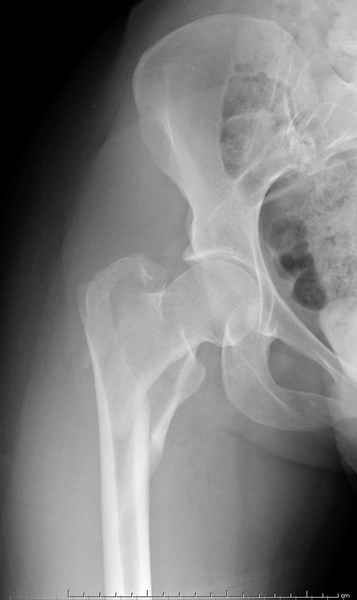

Ap pelvis Rt sub-intra trochanteric Fracture

AP Rt hip

Ap pelvis Rt sub-intra trochanteric Fracture, AP Rt hip, Postop Blade Fixation